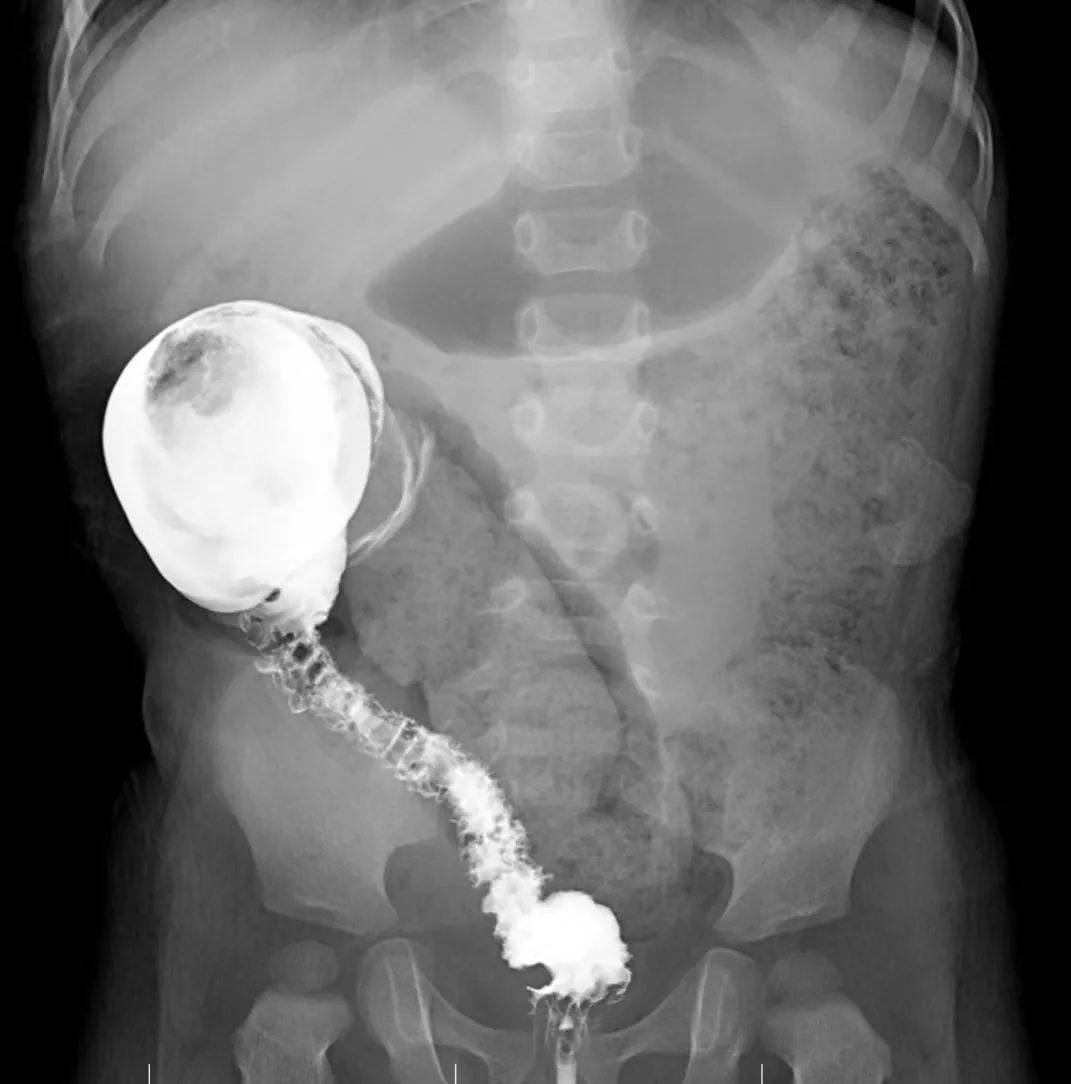

而先天性巨结肠则是靠近菊花那一段肠管因为缺少了神经节细胞,长期处于痉挛细小不干活的状态,肌肉团队缺乏肠道神经的配合,便便到了这里就很难通过而在上方正常的结肠里玩起大塞车,久而久之上方的结肠就如同吹气球般扩张肥厚,变成了「巨结肠」。

看着病历本上孩子因病变肠管长,扩张明显,已经不能做微创手术的诊断。李女士一家最终无奈决定,接受医生建议行开放性手术:在孩子肚子划开一道长长的口子,再把坏死的肠道切掉。

手术利用 3 个 4 mm 切口作为通道,其中一个通道插入腹腔镜的摄像探头,孩子肚子里病变的肠管在显示器上显示得清清楚楚。

这时,周小渔主任从另外两个通道插入微创手术专用的手术器械,在腹腔镜辅助下将发生病变的肠管全部切除,总长约 35 cm,手术全程几乎没有出血。